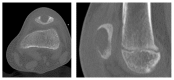

Osteomyelitis of the Patella in a 10-Year-Old Girl: A Case Report and Review of the Literature

The incidence of osteomyelitis constantly declines. While the disease most commonly affects the long bones, involvement of the patella is rarely seen. Due to this rarity and the variable clinical presentation, diagnosis is often delayed. The present case report describes a 10-year-old female patient with a delayed diagnosis of patella osteomyelitis. The diagnostic procedures and the treatment regimen are described. Additionally, a detailed literature review of the available publications reporting osteomyelitis of the patella in children is presented.